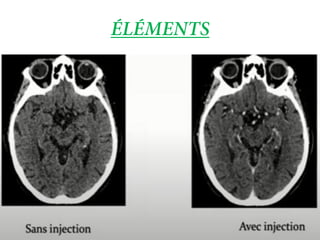

• Utilisés lorsque le contaste naturel en TDM est

insuffisant pour obtenir des informations

• PDCI par voie IV

• IODE : forte absorption des rayons X ( densité

élevée )

• Examen TDM avec injection de PDIC :

C’est la technique la plus utilisee surtout

couramment avec l’agmentation des

frequenes de cancer

Images TDM acquises dans un delai variable

après injection de PDCI en fonction des

structures que l’on souhaite voir opacifiées